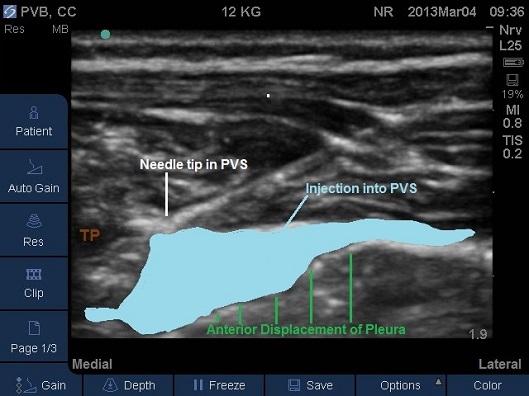

- Correct placement of the needle in the thoracic Paravertebral space should be confirmed by the anterior displacement of pleural upon injection of a small bolus of saline or local anaesthetic (Fig 13-16).

- Once confirmed the required volume of local anaesthetic should be injected.

Fig 14. Paravertebral space entered by needle, pleura displaced anteriorly by local anaesthetic.

Fig 15. Paravertebral space entered by needle, pleura displaced anteriorly by local anaesthetic. TP –transverse process. Local anaesthetic spread marked in light blue